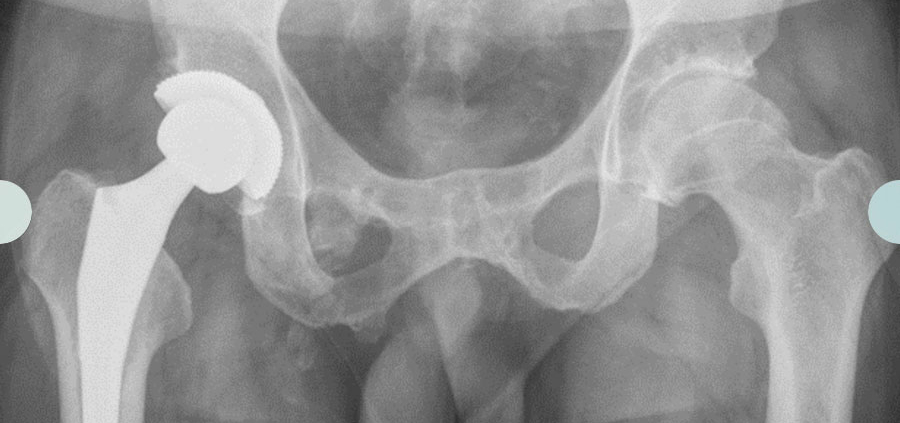

Die Operation selbst wird über einen vorderen kleinen Zugang (ASI) durchgeführt, welcher den wichtigen mittleren Hüftmuskel schont. Vorteile dieser Operationstechnik liegen in einer sehr guten operativen Übersicht, geringen Komplikationsrate und zeitnahen Vollbelastung nach der Operation. Während der Operation wird die Implantation der Prothese mit einem Röntgen-Bildwandler auf korrekten Sitz kontrolliert.